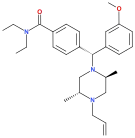

The pharmacodynamic response to an opioid depends upon the receptor to which it binds, its affinity for that receptor, and whether the opioid is an agonist or an antagonist. For example, the supraspinal analgesic properties of the opioid agonist morphine are mediated by activation of the μ1 receptor; respiratory depression and physical dependence by the μ2 receptor; and sedation and spinal analgesia by the κ receptor. Each group of opioid receptors elicits a distinct set of neurological responses, with the receptor subtypes (such as μ1 and μ2 for example) providing even more [measurably] specific responses. Unique to each opioid is its distinct binding affinity to the various classes of opioid receptors (e.g. the μ, κ, and δ opioid receptors are activated at different magnitudes according to the specific receptor binding affinities of the opioid). For example, the opiate alkaloid morphine exhibits high-affinity binding to the μ-opioid receptor, while ketazocine exhibits high affinity to ĸ receptors. It is this combinatorial mechanism that allows for such a wide class of opioids and molecular designs to exist, each with its own unique effect profile. Their individual molecular structure is also responsible for their different duration of action, whereby metabolic breakdown (such as N-dealkylation) is responsible for opioid metabolism.

A new strategy of drug development takes receptor signal transduction into consideration. This strategy strives to increase the activation of desirable signalling pathways while reducing the impact on undesirable pathways. This differential strategy has been given several names, including functional selectivity and biased agonism. The first opioid that was intentionally designed as a biased agonist and placed into clinical evaluation is the drug oliceridine. It displays analgesic activity and reduced adverse effects.[162]

Opioid comparison